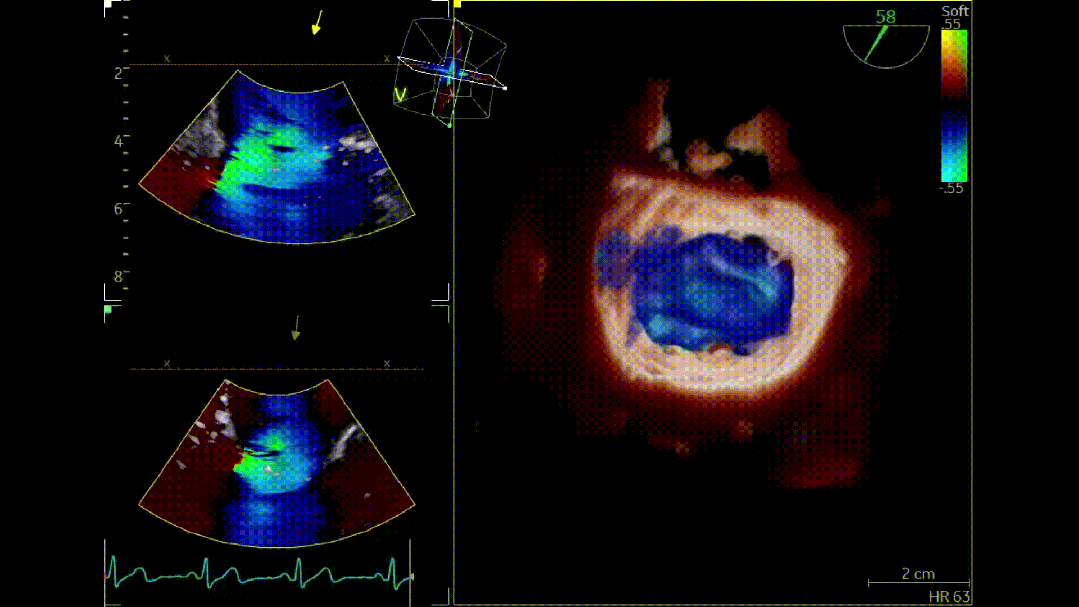

本次培训的“重头戏”—— 两台高难度 TEER 手术沉浸式观摩,将培训氛围推向高潮。手术病例分别为 “P2 宽大脱垂病变” 与 “早期 Barlow 病变”,由厦门大学心血管病医院团队与浙江大学附属邵逸夫医院团队协同完成。术中,专家团队操作精准、配合默契,不仅完美展现了 TEER 技术在复杂病例中的应用优势,更通过实时讲解,让学员直观掌握手术关键步骤、解剖评估要点与应急处理思路。

病例2: